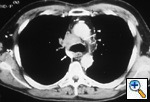

Fig.

53: Computed

tomographic scan of the

chest shows a large mass

in the right paratracheal

area obstructing the

superior vena cava. The

azygous vein (white arrow)

is also obstructed and

multiple small vessels

are seen on the left

side of the mediastinum

(white arrowheads); the

internal mammary veins

are also prominent (black

arrows), T4 N2 M0, stage

IIIB. |